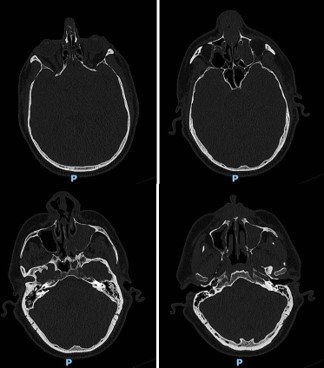

The ostiomeatal complexes were occluded bilaterally, and there was bowing of the nasal septum to the right (Figure 1). He was scheduled for an endoscopic evaluation under anesthesia with nasal biopsy and frozen section analysis. Intraoperatively patient was noted to have fungating masses within bilateral nasal cavities. Multiple biopsies were obtained showing invasive squamous cell carcinoma. The case was terminated and a CT neck with contrast was obtained for surgical planning.

The new CT showed an ulcerated mass within the nasal cavity and a 1.4 cm septal perforation. Fluid and soft tissue were completely opacifying the left maxillary sinus. There was destruction of the nasal bone with the involvement of nasal skin, septal destruction with extension to the hard palate, and an extensive mass inside of the left maxillary sinus without any apparent orbital floor invasion (Figure 2). No cervical or distant metastases were appreciated at the time. The clinical Tumor, Nodal, and Metastasis (TNM) staging for the tumor was noted to be cT4N0M0. We recommended a left maxillectomy, left modified neck dissection with subtotal rhinectomy, and left chimeric scapular free flap for reconstruction.